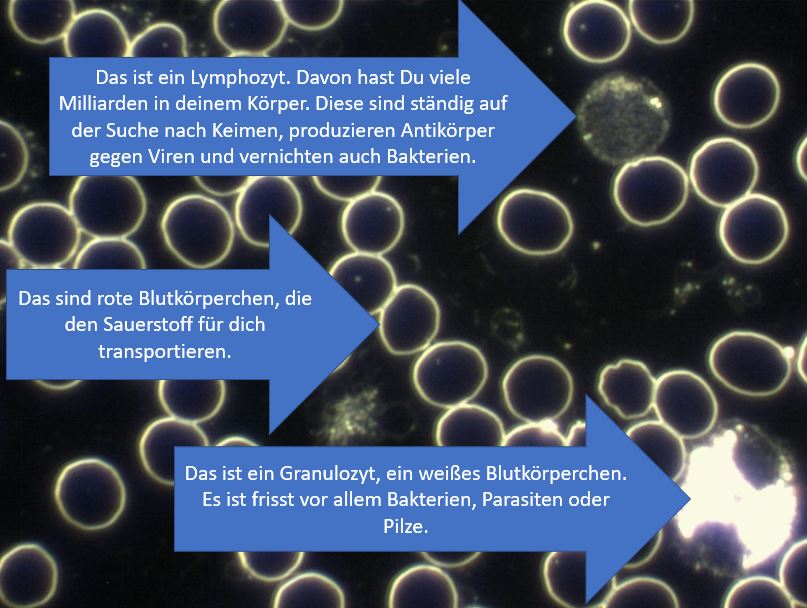

Zum Schluss noch ein abschreckendes Beispiel von Dunkelfeld-Aufnahmen.

Folgendes Bild wurde u.a. auf telegram geteilt:

Wir sehen hier in deutlich geringerer Vergrößerung auch Blut. Allerdings sehen wir hier vor allem den Rand des Bluttropfens (oben). Die Ränder sehen mehr oder weniger fast immer so aus. Was wir hier allerdings sehen ist ein stark verschmutzter Objektträger (helle Objekte ganz oben). Zudem sehen wir Lufteinschlüsse im Präparat.

Das könnte man alles als „Anfänger-Fehler“ bezeichnen. In der Praxis würde ich einem Assistenten anweisen, diese Probe zu verwerfen und eine neue Entnahme durchzuführen.

Aber wir haben noch das Problem, dass solche Bilder gezeigt werden und behauptet wird, dass hier die Folgen einer Corona-Impfung deutlich zu sehen seien, inklusive Nanotechnologie, usw. Ich halte das für blanken Unsinn, dies aus diesem Bild hier abzuleiten.